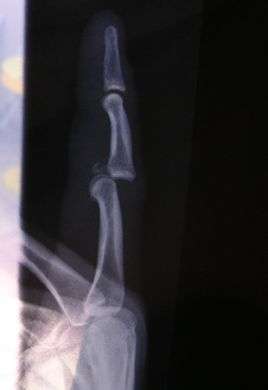

Dislocation of the left index finger

Radiograph of right fifth phalanx bone dislocation- Radiograph of left index finger dislocation